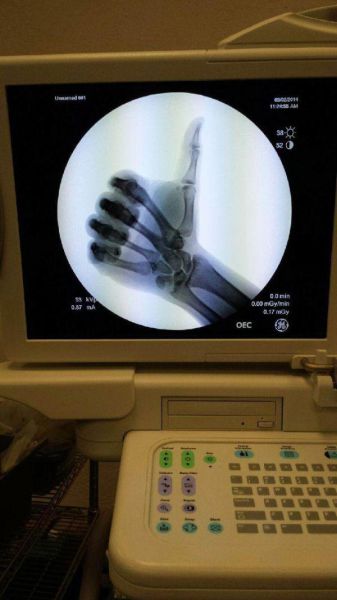

骨が透けてるけど、いえーい!